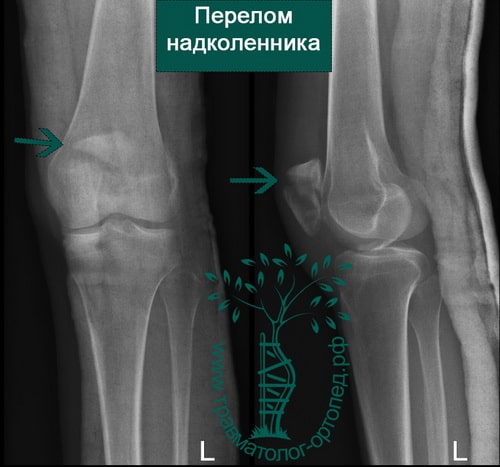

Как и при любой травме коленного сустава для постановки правильного диагноза выполняется рентгенография, на которой-то и можно увидеть перелом. Обычно рентгенографию выполняют в прямой и боковой проекциях, а для диагностики вертикальных переломов выполняют еще и осевую (аксиальную, или Merchant) проекцию.

Прямая (слева) и боковая (справа) проекции, на которых виден горизонтальный перелом надколенника со смещением отломков. Осевая проекция. Вертикальный перелом. Обратите внимание на возникшую в результате смещения ступеньку на скользящей поверхности надколенника.

Осевая проекция. Вертикальный перелом. Обратите внимание на возникшую в результате смещения ступеньку на скользящей поверхности надколенника.Иногда для более точного диагноза могут потребоваться компьютерная и/или магнитно-резонансная томография, но, в подавляющем большинстве случаев, достаточно рентгенографии.